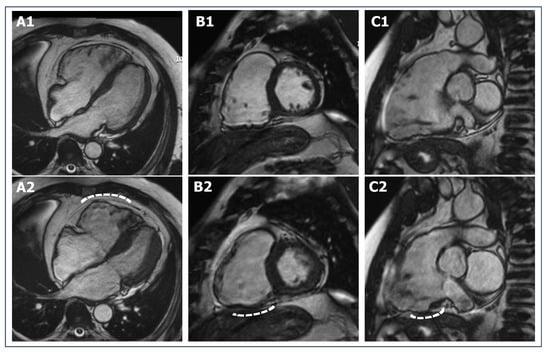

- Petersen, S.E.; Selvanayagam, J.B.; Wiesmann, F.; Robson, M.D.; Francis, J.M.; Anderson, R.H.; Watkins, H.; Neubauer, S. Left ventricular non-compaction: Insights from cardiovascular magnetic resonance imaging. J. Am. Coll. Cardiol. 2005, 46, 101–105. [Google Scholar] [CrossRef]

- Gati, S.; Chandra, N.; Bennett, R.L.E.; Reed, M.; Kervio, G.; Panoulas, V.F.; Ghani, S.; Sheikh, N.; Zaidi, A.; Wilson, M.; et al. Increased left ventricular trabeculation in highly trained athletes: Do we need more stringent criteria for the diagnosis of left ventricular non-compaction in athletes? Heart 2013, 99, 401–408. [Google Scholar] [CrossRef] [PubMed]

- Luijkx, T.; Cramer, M.J.; Zaidi, A.; Rienks, R.; Senden, P.J.; Sharma, S.; van Hellemondt, F.J.; Buckens, C.F.; Mali, W.P.; Velthuis, B.K. Ethnic differences in ventricular hypertrabeculation on cardiac MRI in elite football players. Neth. Heart J. 2012, 20, 389–395. [Google Scholar] [CrossRef] [PubMed]